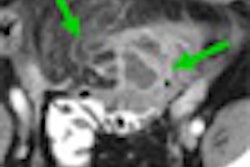

In 2006, Hausleiter and colleagues took a different path to the question, examining the prevalence and characteristics of noncalcified plaque in 161 symptomatic individuals using 64-detector-row CT angiography (CTA) (Journal of the American College of Cardiology, July 2006, Vol. 18:2, pp. 312-318).

Patients were scanned using MDCT at 32 x 0.6-mm intervals. Significant disease couldn't be ruled out in 33% of the cohort; noncalcified plaque was present in 44% of the remaining patients. In 10% of the 63 patients with CAC scores of zero, noncalcified plaques were the only ones responsible for coronary artery disease, Lima said of the study.

"Hausleiter et al showed that 16% of 63 patients with calcium scores of zero had noncalcified plaques," Lima said. "None of this is surprising to us, but it's good to have in mind this excellent data when you go to symptomatic people from the [Coronary Artery Evaluation Using 64-Row Multidetector Computed Tomography Angiography (CORE) 64 trial]."